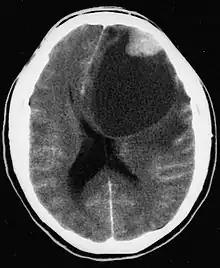

| CT scan of a brain with pleomorphic xanthoastrocytoma. The classic radiographic appearance is one of a superficially situated tumor, here a mural nodule, associated with an underlying cyst. |